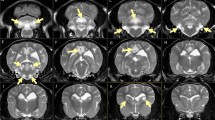

Except for the dorsoventral flattening of the thorax, no gross abnormalities were noted at necropsy. On histopathological examination, lesions were confined to the central nervous system. In the white and grey matter of the brain, blood vessels were surrounded by numerous short, perpendicular orientated, hypereosinophilic, amorphous intra-astrocytic RFs (Supplementary Information File S3A). These RFs were also found in the astrocytic endfeet in the subpial tissue and in some subventricular locations. All RFs were strongly immunopositive for GFAP (Supplementary Information File S3B). There was proliferation of abnormal astrocytes with large nuclei, prominent nucleoli and glassy eosinophilic to pale cytoplasm. All neuronal populations as well as oligodendroglial nuclei showed no abnormalities.

At all levels of the spinal cord, RFs were found in both white and grey matter, mostly perivascular and subpial. Moderate numbers of hypertrophied astrocytes were noted.